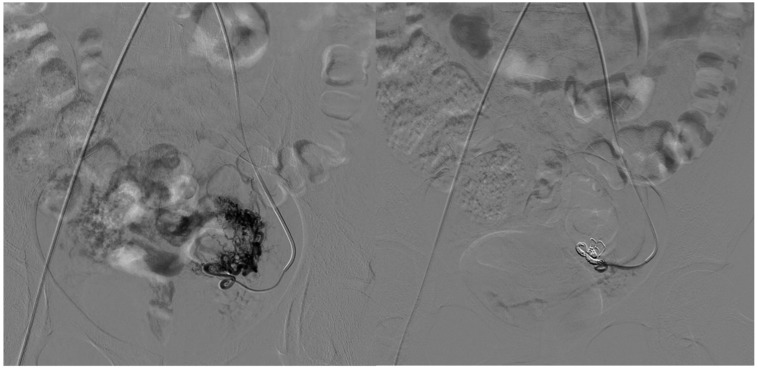

背景:颅外动静脉畸形(AVMs)是一种罕见的先天性血管异常,通常由于疼痛、出血或功能障碍等症状而需要血管内治疗。血管内栓塞包括动脉栓塞、静脉栓塞或联合栓塞;然而,复发仍然是主要的挑战。我们回顾性评价单纯动脉栓塞与动静脉联合栓塞治疗颅外动静脉畸形的技术成功、安全性和临床结果。材料和方法:本单中心回顾性研究纳入14例患者(平均年龄31.8±21.7岁;在2017年至2023年期间,有症状的颅外AVMs (Schobinger II期)治疗的患者占64%(女性)。血管造影对AVMs进行分类(Yakes分类),并通过动脉或联合通路进行栓塞治疗。主要终点是技术成功(定义为血管造影病灶闭塞),次要终点包括临床复发和手术相关并发症。随访包括临床和多普勒超声评估。结果:9例(64%)患者单独行动脉栓塞术;5例(36%)接受动脉和静脉联合栓塞,包括直接穿刺注射聚月桂醇。所有病例均取得了技术上的成功(100%)。2例患者(14%)出现临床复发,均来自单纯动脉组。一个主要的并发症(舌缺血)发生在一个病人身上(7%)。联合治疗组无并发症及复发。统计学分析显示两组患者复发率及并发症发生率无显著差异。

Results: Nine patients (64%) underwent arterial embolization alone; five (36%) received combined arterial and venous embolization, including Lauromacrogol injection via direct puncture. Technical success was achieved in all cases (100%). Clinical recurrence occurred in two patients (14%), both from the arterial-only group. One major complication (tongue ischemia) occurred in a single patient (7%). No complications or recurrences were observed in the combined treatment group. Statistical analysis showed no significant difference in recurrence or complication rates between groups.